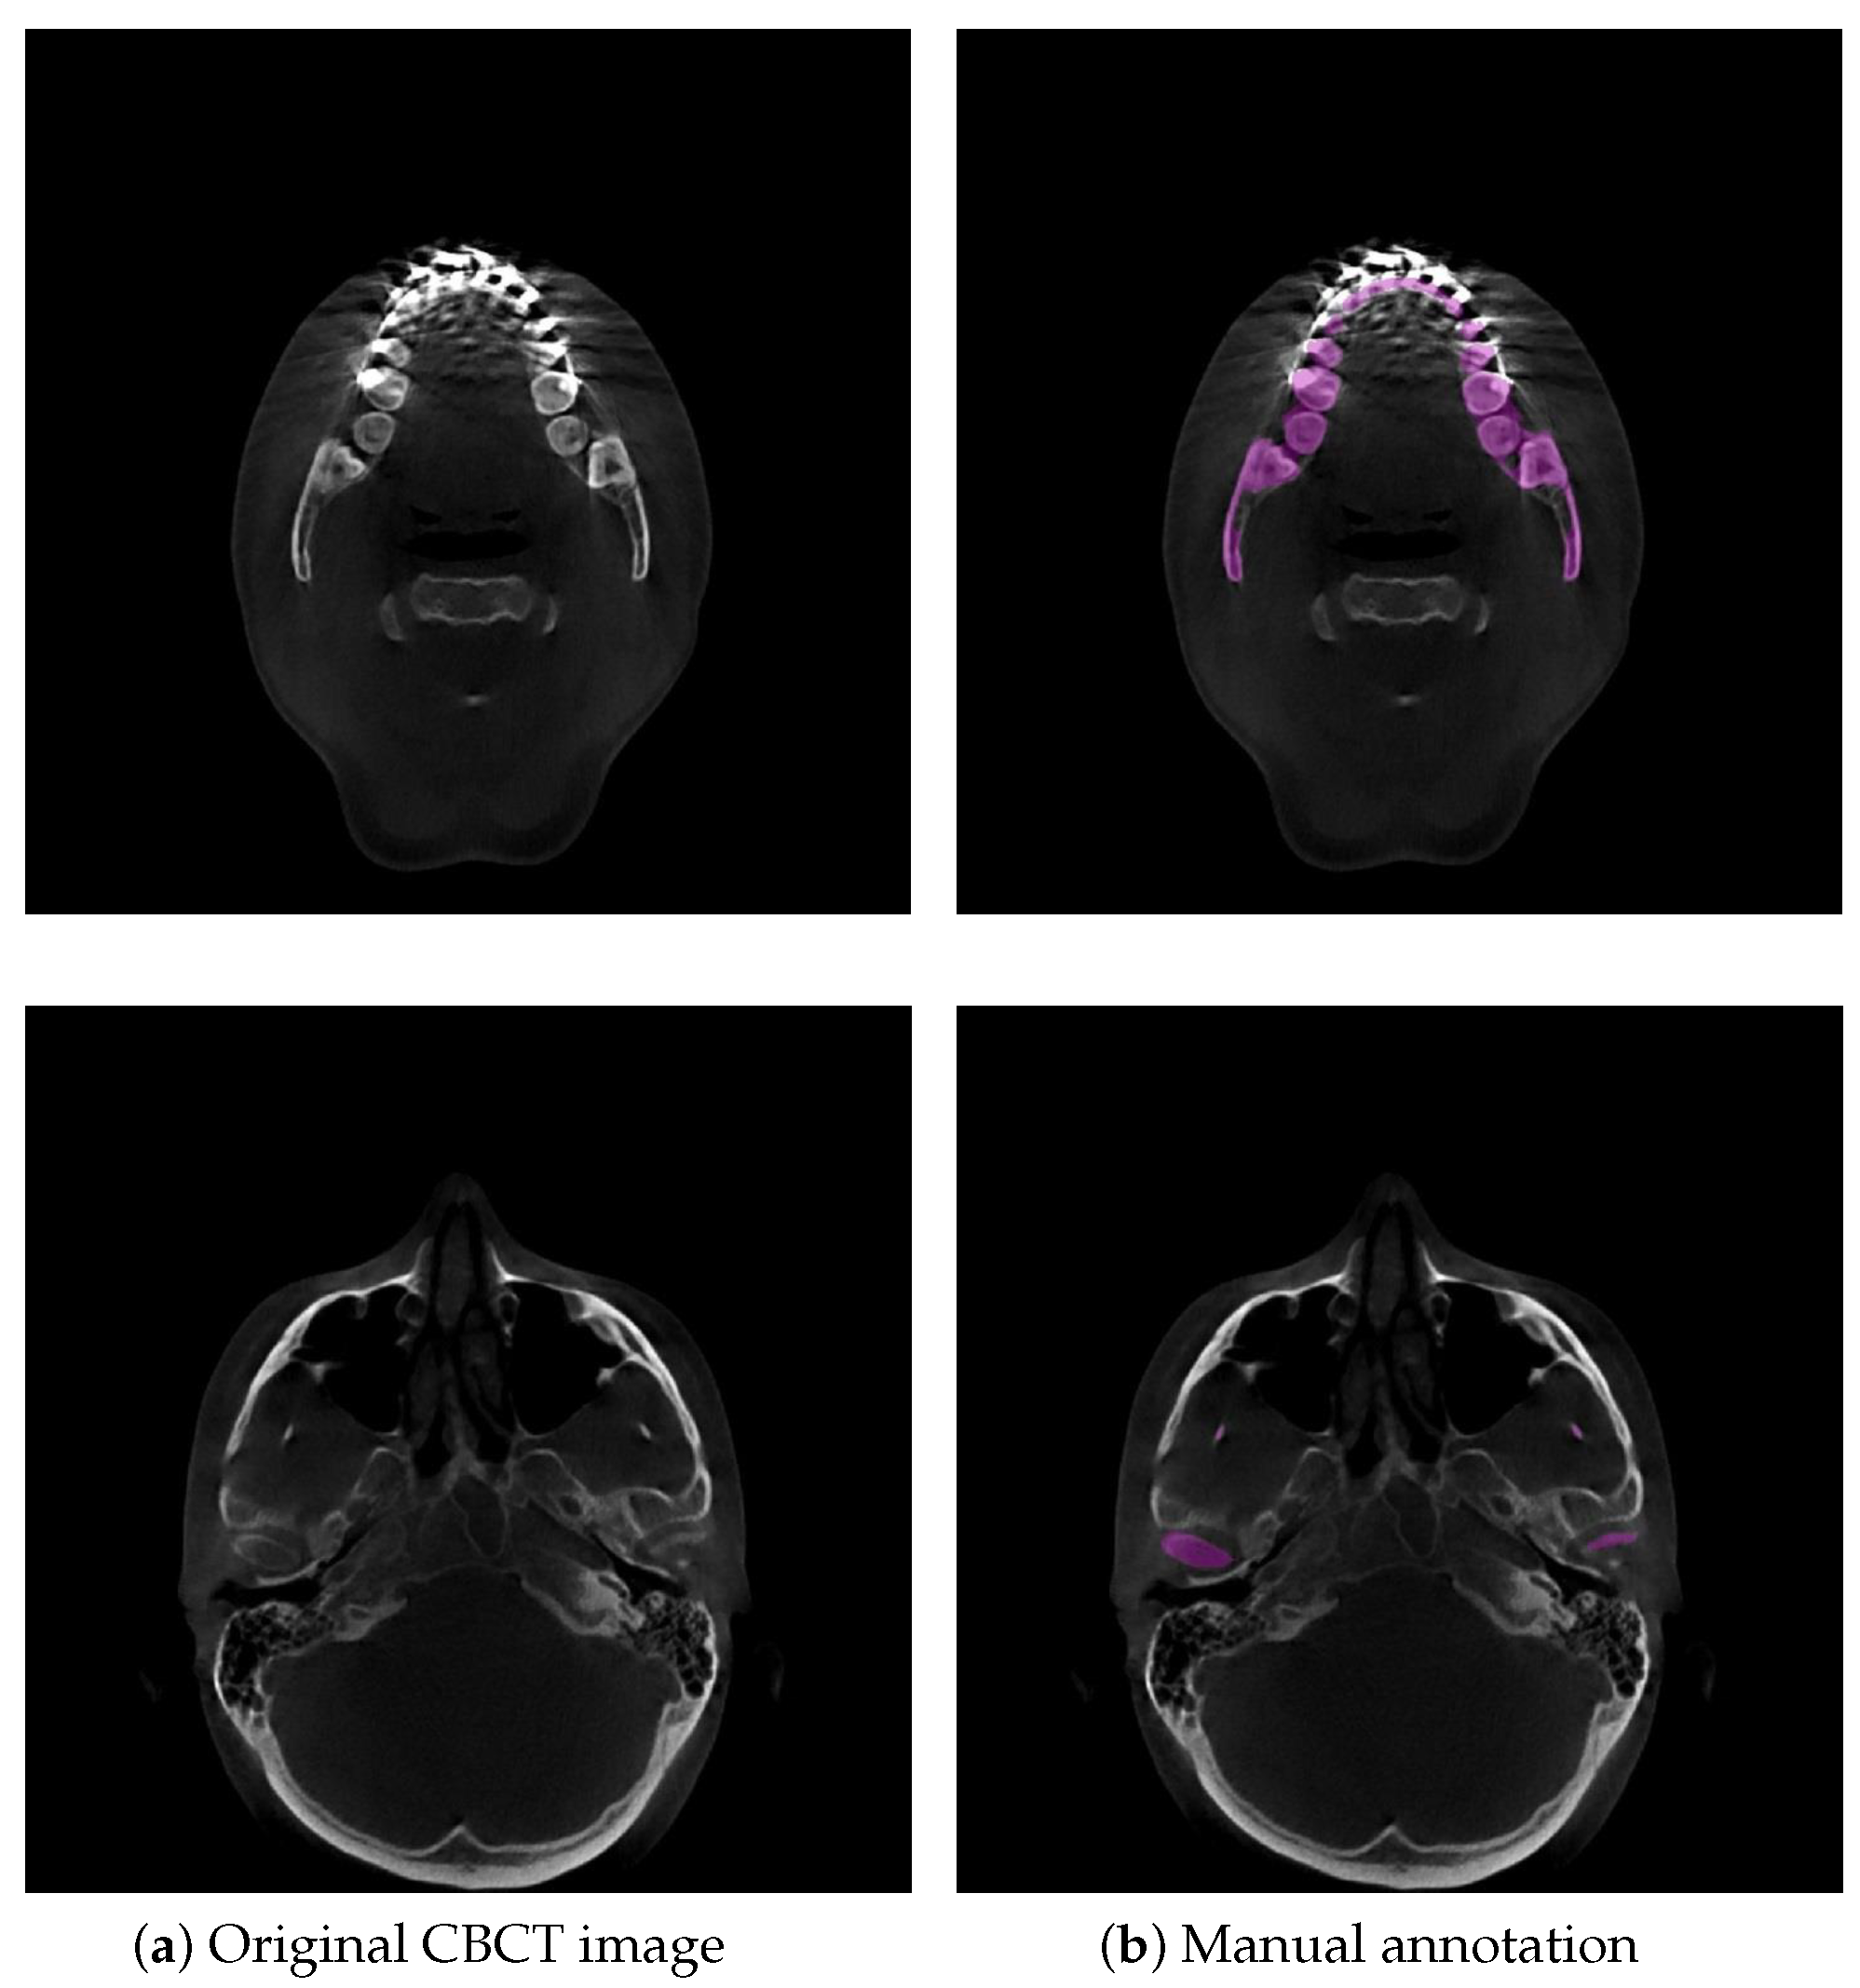

Currently, the three-dimensional (3D) virtual surgical planning (VSP) technique is commonly used for oral and maxillofacial surgery (OMFS), and planning since it allows for pre- or postoperative simulation of surgical options [1]. 3D surface models of the mandible in 3D VSP are created and superimposed to visually and quantitatively demonstrate the orthodontic/orthognathic changes and provide postoperative follow-up of patients with cranio-maxillofacial deformities [1]. Cone-beam computed tomography (CBCT) is widely applied in 3D VSP because of its lower radiation dose and faster scanning time than conventional CT [2]. In orthodontic or orthognathic treatment, the dentist or maxillofacial surgeon needs visual information about the location and movement of their patient’s teeth and mandible. A requirement for this process is to accurately segment the mandible from the dental CBCT scans and then to generate 3D surface mandible model. Therefore, accurate mandible segmentation plays an important role in 3D VSP for OMFS. Dental CBCT scans are noisier and have more metal artifacts than conventional CTs because dental CBCTs use a low-radiation technique and teeth, dental braces in orthodontic treatment and metal implants in orthognathic treatment are higher attenuation materials, easily leading to high noise and strong metal artifacts in the visual impression of the scans [3]. The boundaries of mandibles are difficult to be identified since dental braces and metal implants badly affect the image quality in CBCT [4], as shown in Figure 1. Additionally, low contrast in the condylar process very often leads to ambiguous and blurred boundaries in CBCT scans because of its low radiation dose, as illustrated in Figure 1. Consequently, the main difficulty in orthodontics or orthognathic visualization is precise mandible segmentation in CBCT scans. Currently, manual segmentation for 3D modeling of the mandible is widely adopted in clinical practice, but this is a time-consuming and labor-intensive approach so that it is impractical to perform on a large number of subjects. Moreover, manual segmentation often suffers from large interoperator variability (Dice score of 94.09 % between two clinical experts) [5], which directly influences the quality of treatment planning. To date, there are still no reliable automatic segmentation approaches that can adapt to badly affected CBCT scans. Accordingly, it is meaningful to develop an accurate and automatic technique to segment the mandible for orthodontic or orthognathic treatment from CBCT images.

Figure 1. Example illustrations that challenge mandible segmentation in CBCT images. (a) Original CBCT image. The mandible and teeth appear with almost invisible boundaries. (b) Example of manual annotation. Low contrast often appears in condyles. The purple region indicates the manual annotation of the mandible.